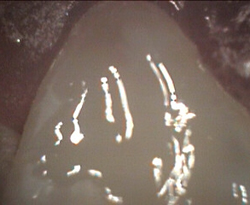

Primary first molar deep cavity pulp exposure pulp cleaning process

pulpotomy complete and lasered clean white filling being added

Restored